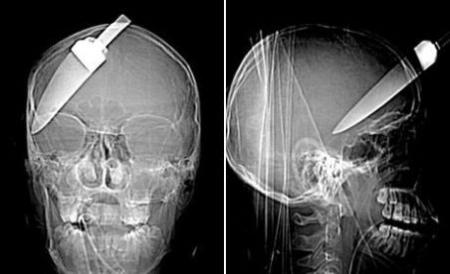

Bărbatului nu-i trecea prin minte că are o lamă în cap. Tot ce îşi aminteşte este că în anul 2005 a fost la o petrecere, unde, băut fiind, s-a luat la bătaie cu un alt petrecăreţ. Acesta i-ar fi înfipt atunci un cuţit în craniu, dar sub efectul alcoolului victima nu a acordat importanţă incidentului. A doua zi când s-a trezit a crezut că doar s-a lovit.